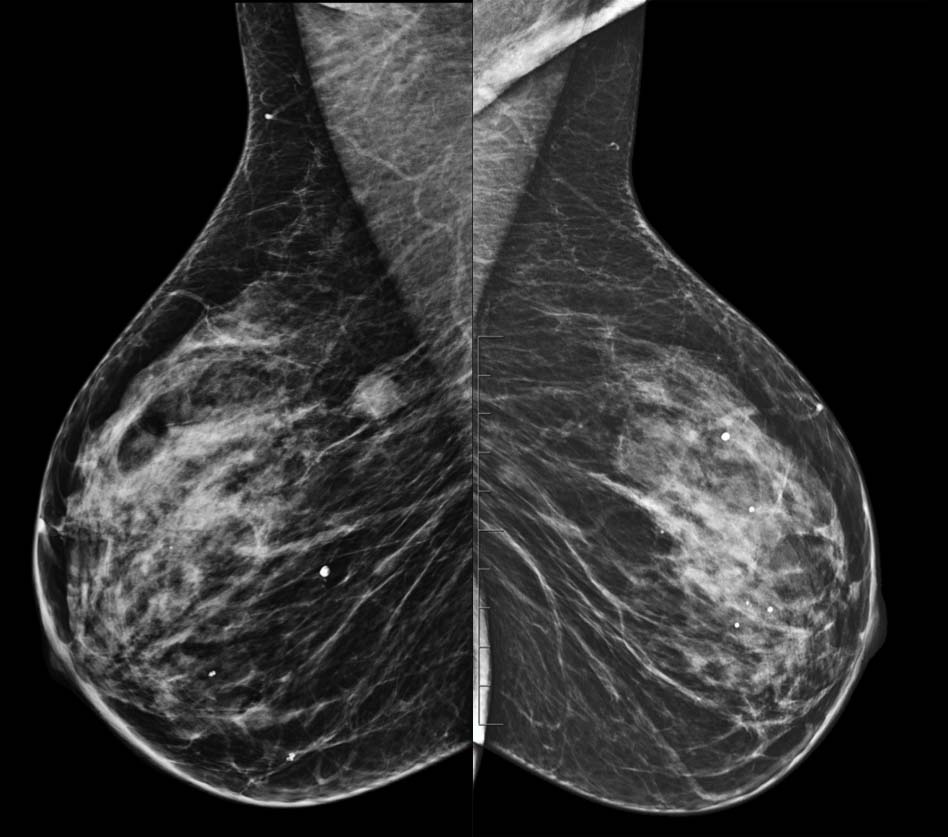

- Control previo en el PPDCMA (Programa de Prevención del Cáncer de Mama en Aragón) en 2019 normal. Control actual en las imágenes.

- A. BI-RADS 0. Hay que completar estudio con RM con contraste.

- B. BI-RADS 1. No hay que hacer nada porque el nódulo tiene aspecto benigno.

- C. BI-RADS 4. Haremos biopsia con aguja gruesa (BAG) del nódulo.

- D. BI-RADS 2. Haremos punción con aguja fina (PAAF) del nódulo.

- E- BI-RADS 3. Control con ecografia mamaria en 6 meses.